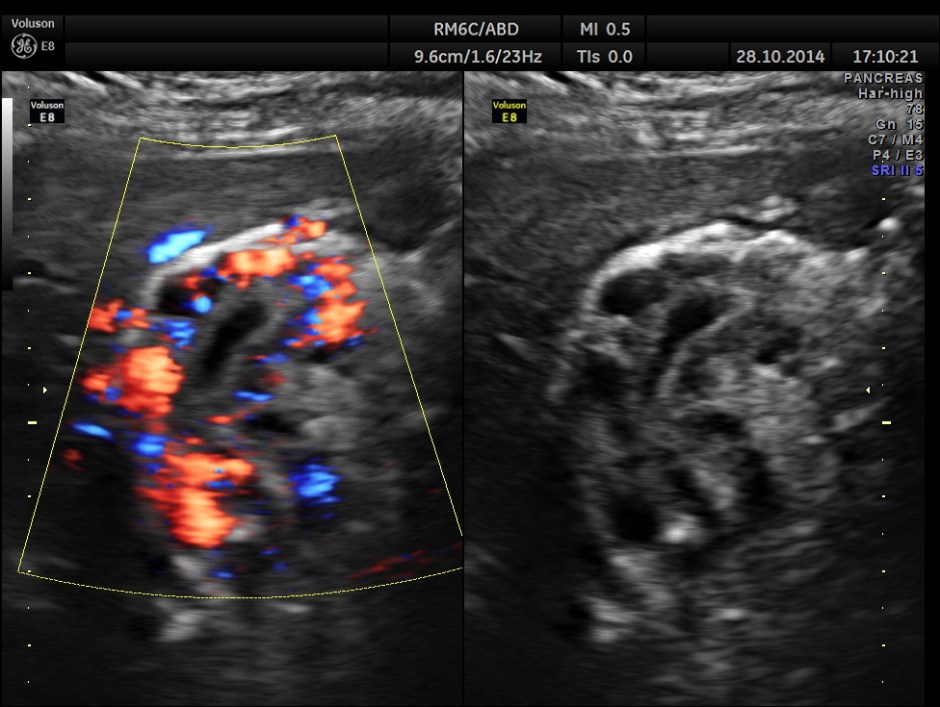

Colour flow imaging of the same

Main portal vein show flow reversal ( blue colour ) – centri-fugal flow suggestive of portal hypertension.

Epigastric varices are also seen.